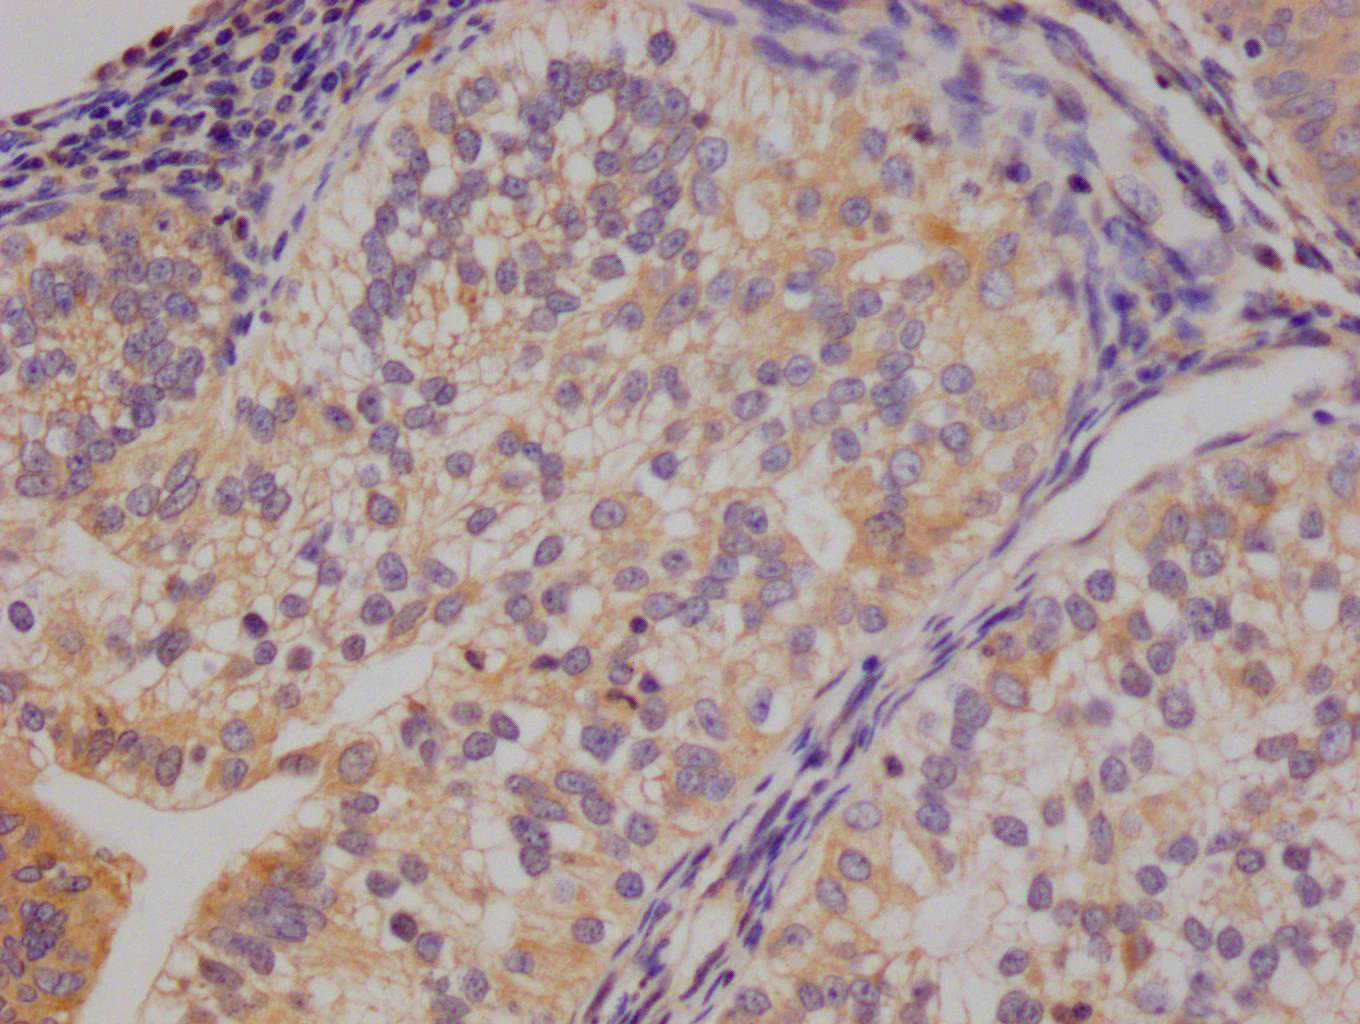

Gel: 8%SDS-PAGE, Lysate: 40 μg, Lane: K562 cells, Primary antibody: CSB-PA051152(CYP2D6 Antibody) at dilution 1/200, Secondary antibody: Goat anti rabbit IgG at 1/8000 dilution, Exposure time: 5 minutes